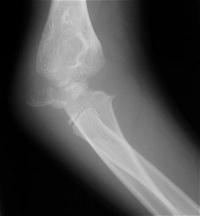

Five years later, he has limited motion (E/F 35/100) and painful clicking with elbow flexion and extension.

Click for larger image

Plain films show humeral osteophytes and posttraumatic changes of the capitellum and radial head.